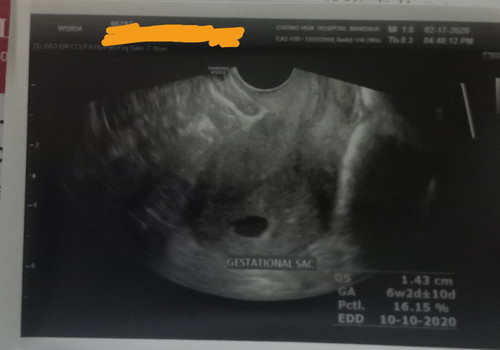

Is it normal to have only a gestational sac seen in my sonography at 6 weeks and 2 days?

ganyan dn po ako...6weeks 3days gestational sac palang wala pa po yolk sac

Yes, 8-9 weeks with visible embryo na